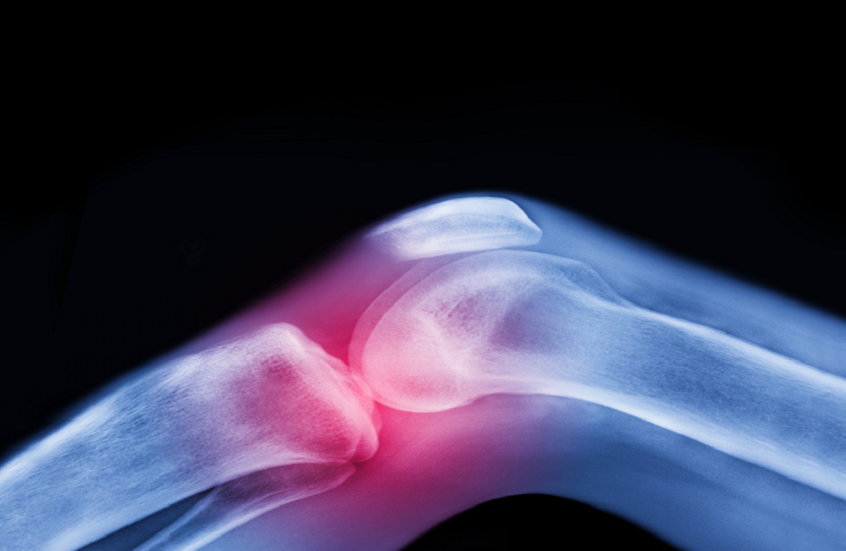

تعتبر آلام المفاصل وتيبّس الركبتين وأوجاع الوركين من الشكاوى الشائعة بين كبار السن، وغالبا ما يُقبل بها كجزء طبيعي من أعراض الشيخوخة.

ولا يعتبر الفصال العظمي مجرد تآكل ميكانيكي للمفصل، بل مرضاً يؤثر على جميع مكوناته: السائل الزلالي والغضروف والعظم والأربطة والعضلات المحيطة، وحتى الأعصاب التي تدعم الحركة. وتستهدف الحركة المنتظمة جميع هذه العناصر، وتحافظ على صحة المفصل بكفاءة.

ويفتقر الغضروف، وهو طبقة واقية تغطي أطراف العظام، إلى إمدادات الدم المباشرة ويعتمد على الحركة للبقاء صحيا. فهو يعمل مثل الإسفنجة: ينضغط عند الحركة، فيخرج السوائل ويعيد امتصاص المغذيات، ما يحافظ على مرونة المفصل وصحته.